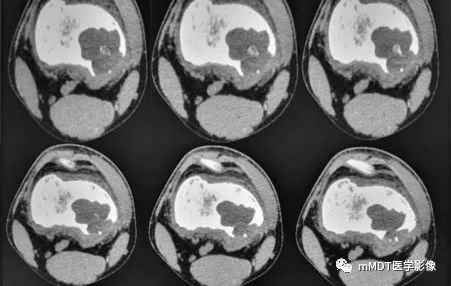

病史:15岁男性,右膝不适2年,行走及上楼时疼痛不明显。查体:右膝内侧膨隆,屈曲略受限,局部皮温正常,皮肤完整。影像资料如下:

CT横断面软组织窗

CT见病变位于股骨远端干骺端,呈分叶状、偏心膨胀性生长,密度欠均匀,整体低于肌肉密度,部分区域密度接近水,其内可见点状、线状、弧形、圆形的高密度影,大部分边缘硬化,局部深侵蚀骨内膜,局部骨壳不完整。MR上,T1WI信号略低于肌肉,T2压脂呈现不均匀高信号,未见明确软骨小叶结构及纤维分隔,周围可见水肿。